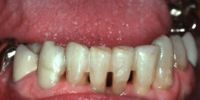

Este paciente se presentó con la queja principal de incomodidad en el funcionamiento de los dientes anteriores inferiores. Nótese la pérdida y recesión de encía.

La queja principal de este paciente era la incomodidad durante el funcionamiento de los dientes anteriores inferiores. Nótese la pérdida y recesión de encía. Todos los incisivos tenían grado 2 de movilidad.

En este caso, el paciente presenta una destrucción periodontal grave del segmento anterior maxilar izquierdo que incluye los incisivos y el canino. El incisivo lateral y el canino tienen un grado 2 de movilidad y una pérdida de masa ósea de más del 60%. El paciente se queja de dolor durante la masticación e incomodidad en los dientes la mayor parte del tiempo.